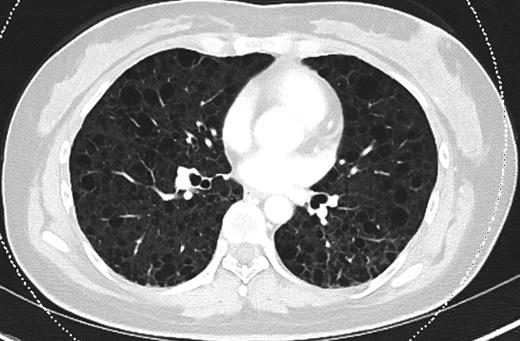

Since discharge from our institution, the patient remains independent of oxygen supplementation. Due to a severe perturbation in her diffusing capacity of the lung for carbon monoxide (DLCO), she was started on sirolimus, a treatment for LAM. Her most recent pulmonary function testing (PFT) revealed a DLCO of 41% predicted and a 6-min walk culminated in desaturation from baseline pulse oximetry of 98–80%. A representative section from her most recent chest CT, performed 8 months after discharge, is shown in Fig. 3.

CT chest (axial slices in lung window) demonstrating interval resolution of pneumothoraces and persistent, diffuse numerous thin-walled pulmonary cysts without cardiophrenic sparing.